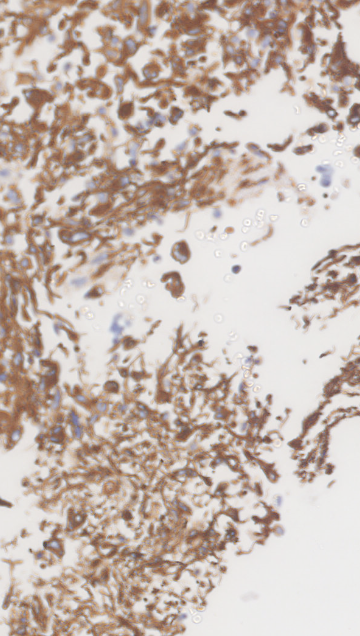

The data presented in this study have been acquired from digital images of immunohistochemistry stainings that were performed on archival tissue obtained from the neurobiobank of the Division of Neuropathology and Neurochemistry at the Medical University of Vienna. Stainings have been performed according to standard procedures (citep \@BBN(Guo et al., 2024; Schwaiger et al., 2023)). Figure 11 (a)-(c) shows a tumour biopsy of a gliosarcoma patient stained for the astrocyte marker GFAP (brown signal, cytoplasmic localization) and counterstained with Hematoxylin (blue signal, nuclear localization). Figure 3 (d)-(e) shows fetal cerebellar tissue stained for the epigenetic mark H3K27me3 (brown signal, nuclear localization) and counterstained with Hematoxylin (blue signal, nuclear localization). The stained sections have been digitalized on a NanoZoomer 2.0-HT digital slide scanner C9600 (Hamamatsu Photonics, Hamamatsu, Japan). The corresponding software NPD.Viewer2 was used to export the scanned images to tiff files. Here, we performed individual scans of a selected imaging area with different numbers of focus points. We chose either 1, 3 or 9 focus points while not changing the spatial settings for the selected field of interest. The image with 9 focus points, allowing the highest resolution, serves as the reference image.

Refer to caption

(a) Reference

(b) (18.6, 0.80, 0.10)

(c) (23.6, 0.91, 0.33)

(d) Reference

(e) (22.9, 0.81, 0.11)

(f) (27.0, 0.87, 0.22)

Figure 11: Data acquired with a slide scanner and 9 (a)(d), 3 (b)(e) and 1 (c)(f) focus points. The image with 999 focus points serves as a reference here. PSNR and SSIM misjudge the tiny spatial misalignment and therefore favor the blurry images with 1 focus point. LPIPS is able to ignore these spatial misalignments.

FR-IQA mismatches

Although the spatial settings for the selected scan area of interest were not changed during the experiment, the physical performance of the scanner showed slight spatial deviations of the selected area between individual scans and thus does not allow for high spatial accuracy during re-scanning processes. PSNR and SSIM fail to correctly assess the images in Figure 11 as they are very sensitive to that kind of misalignments. Whereas clearly the scan with 3 focus points corresponds much better to the reference as the blurred scan with 1 focus point, see (b) and (e) versus (c) and (f), both measures incorrectly judge the blurred scan as better. This wrong judgement due to a tiny spatial change is very problematic in the respective framework, as it is impossible to guarantee completely exact spatial alignment, even if no other settings had been changed during the scanning process. LPIPS is able to correctly judge the rank of quality here.